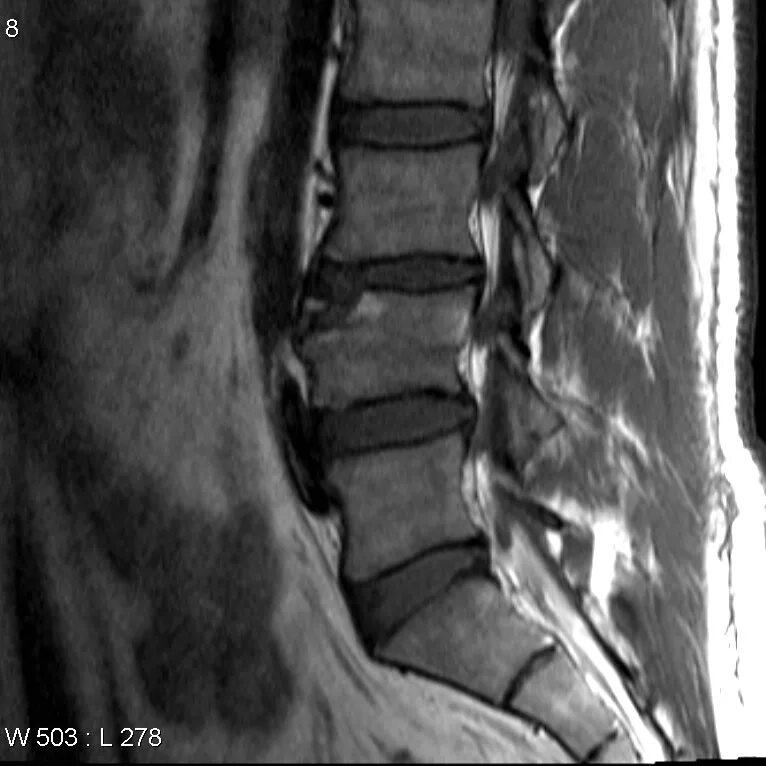

Субхондральный склероз замыкательных пластинок тел позвонков l1-s1. склероз замыкательных пластинок l3-s1. замыкательные пластины l1-s1. modic мрт.

Замыкательные пластины тела позвонков поясничного отдела. дегенеративные изменения позвонков мрт. субхондральный склероз замыкательных пластин тел позвонков.

Modic 1 мрт. классификация modic мрт позвоночника. modic 3 на мрт. остеомиелит позвоночника на кт.

Склероз смежных замыкательных пластинок. субхондральный склероз позвоночника. субхондральный остеосклероз замыкательных пластинок тел позвонков. остеосклероз позвоночника мрт.

Склероз замыкательных пластин l1-s1. субхондральный склероз замыкательных пластин th2-th12. modic 1 мрт. субхондральный склероз замыкательных пластин l 1 l 3.